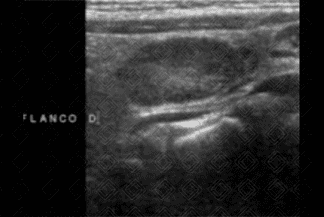

Texto alternativo para a imagem Figura 1. Créditos: Dra. Elazir Mota - Rio de Janeiro/RJ

Descrição das figuras 1 e 2: Ultrassonografia de abdome com múltiplos e grandes linfonodos mesentéricos, hipoecogênicos, com espessamento de alças associado (seta vermelha). Ao estudo com Doppler colorido podemos observar aumento da vascularização do mesentério, sugerindo processo inflamatório/infeccioso. [cms-watermark]

• Na ultrassonografia de abdome: Observam-se múltiplos e grandes linfonodos mesentéricos, hipoecoicos, com aumento da ecogenicidade da gordura mesentérica. Vale destacar que esses linfonodos possuem morfologia e vascularização preservadas ao Doppler colorido. Na população pediátrica, o exame de escolha será a ultrassonografia de abdome.